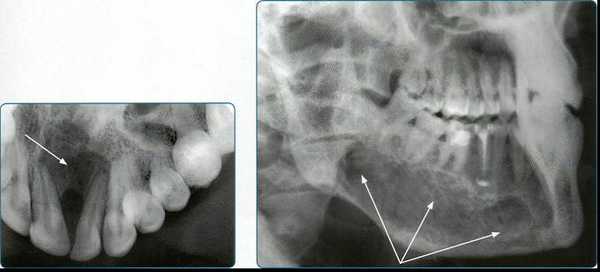

Кроме того, стоматологи традиционно «видят» только зону деструкции и совершенно не обращают внимания на зону интоксикации, представленную перифокальным остеосклерозом. Данный элемент изображения, представленный зоной уплотнения костной ткани по краю деструкции, указывает на наличие хронической интоксикации и очерчивает истинную протяженность патологического очага (рис. 3) . Перифокальный остеосклероз соответствует состоянию хронического абсцедирования и не встречается в случае наличия стерильных деструктивных процессов (доброкачественные опухоли, кисты различного генеза (рис. 4) , апикальных гранулем вне состояния нагноения (экзацербации).

Рис. 3. Внутриротовой снимок зуба 24, хронический периапикальный абсцесс (К04.6), визуально определяется зона деструкции костной ткани с характерным перифокальным склерозом.

Рис. 4. Внутриротовой снимок зуба 44, радикулярная киста (К04.7), воспалительная ремоделяция перифокальной костной ткани отсутствует (пояснение в тексте).